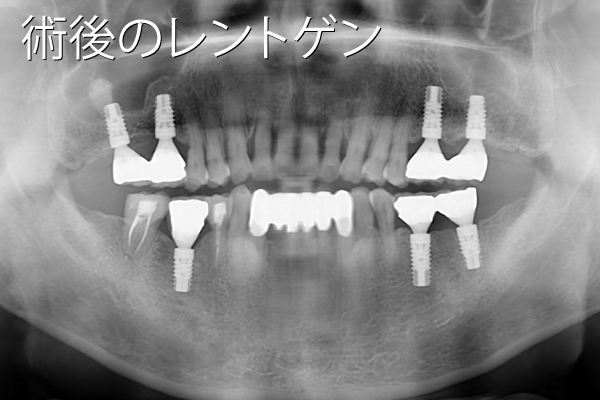

- 性別年齢

- 女性:51歳

- 治療内容

- インプラントを上下顎の奥歯に12本

- 金額

- 517万円(税込)

- 来院理由

- 歯周病が進行してきたため、噛めなくなってきた。インプラントを含めて総合的にきちんとした専門医の治療を受けたい。

- 施術の

副作用

(リスク) - 経過とともになくなりますが、術直後に腫れや違和感を感じることがあります。